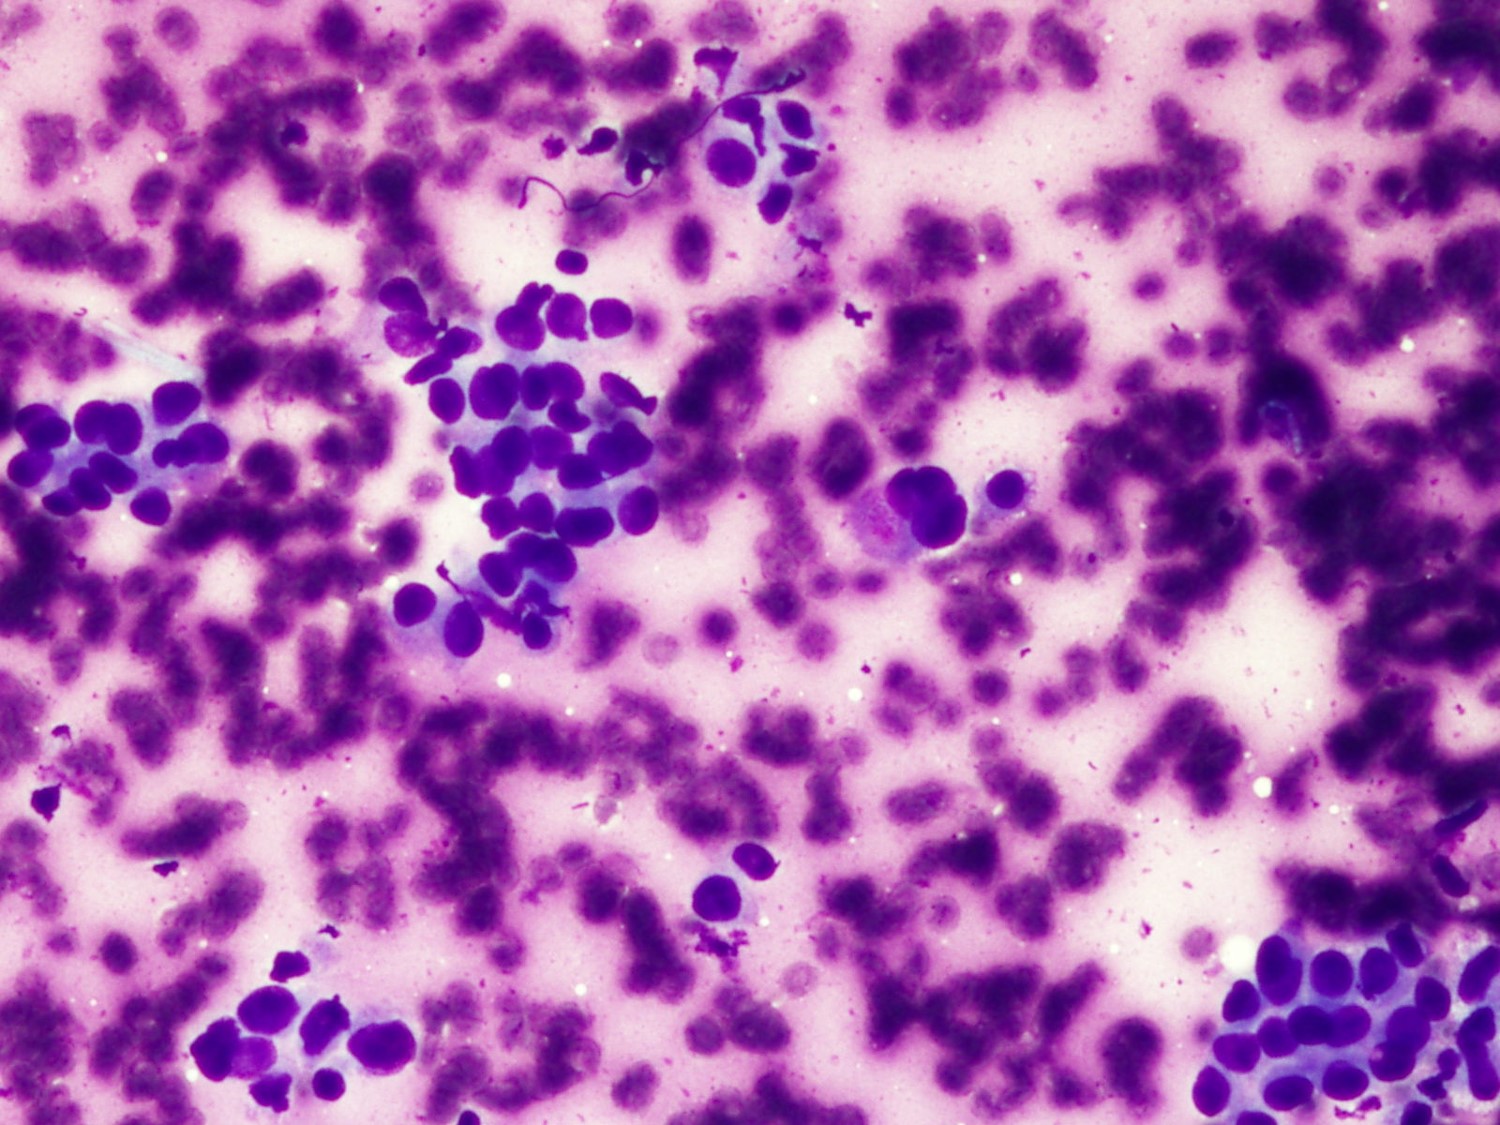

Paciente varón de 79 años sin antecedentes patológicos destacables que presenta cuadro de tres meses de evolución de dolor lumbar irradiado por trayecto L4. Se realiza Resonancia Magnética que muestra una masa osteolítica en muro posterior de L4 con captación de contraste.

Hombre de 59 años, bronquítico crónico que refiere aumento del volumen mamario bilateral. Con una TC que informa masa tumoral en mediastino medio, voluminosa, sólido- quística, con extensa necrosis tumoral y adenopatías mediastínicas paratraqueales de tamaño significativo. Se realizar una PAAF guiada Ultrasonografía Ecobroncoscópica (EBUS) para el diagnóstico definitivo.

Dona de 77 anys amb lesió umbilical costrosa. Onfalitis crònica. No història de síndrome tòxica ni antecedents patològics importants. Es practica PAAF de la lesió umbilical. Posteriorment refereix discret augment del perímetre abdominal desde fa mesos. En la ECO abdominal: abundant quantitat de líquid ascític que es punciona obtenint 20 cc. de líquid serós.